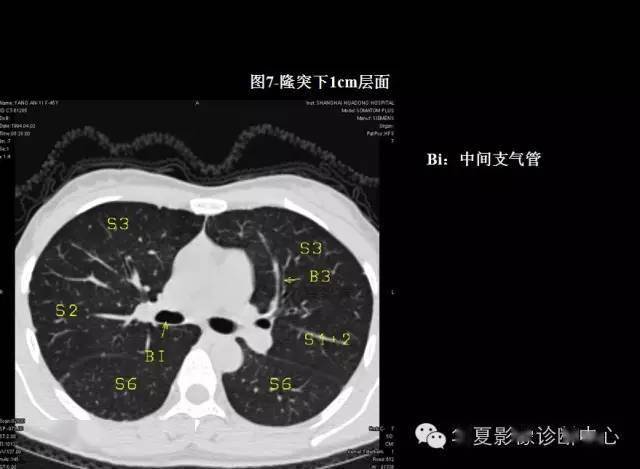

肺部感染ct太难学看完这篇干货不信你还不会

肺ct片子怎么看图片

肺ct图片怎么看图解

怎么看肺部ct片子图解

肺部ct怎么看图解

ct怎么看图解肺部

正常肺部ct怎么看图解

正常肺ct片图片图解